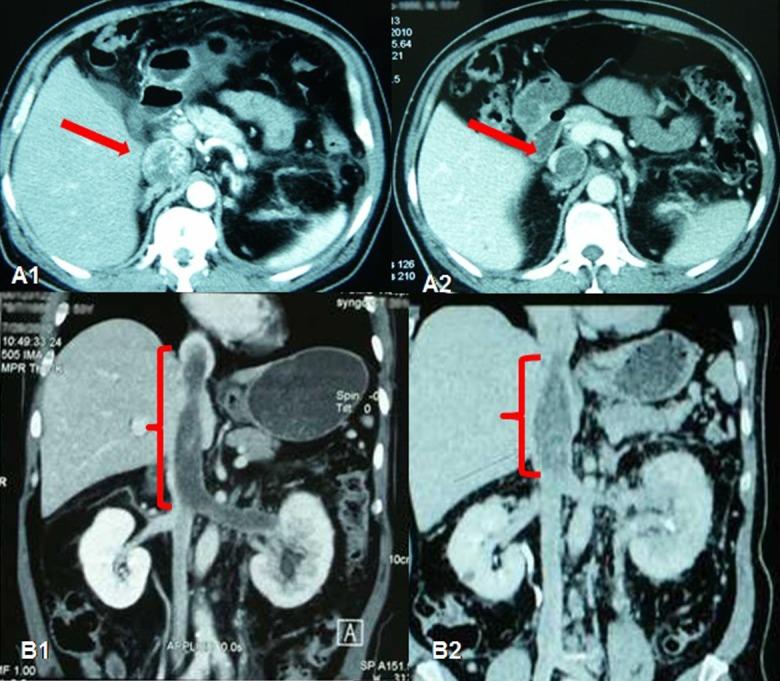

Among the 18 patients there were 13 male and 5 female, with a median age of 54.6 years. The objective response rate (ORR) of the operation on the selected patients is very high (94.4%), including 4 cases (22.2%) of partial response (PR) and 13 cases (72.2%) of stable disease (SD). After preoperative sorafenib treatment, the average tumor size of the 18 patients decreased from 7.8 cm (ranging from 3.6 to 19.2 cm) to 6.2 cm (ranging from 2.4 to 16.8 cm), and the median value of average tumor CT value decreased from 61HU to 52 HU. Among the 5 patients who had IVC tumor thrombi, the grades of tumor thrombi in 2 patients who were grade II before sorafenib treatment became grade I and grade 0 respectively, 2 patients of grade III both became grade II.

Preoperative neoadjuvant therapy with sorafenib for high risk RCC patients can significantly decrease primary tumor volume as well as tumor thrombus, which could help the nephron-sparing surgery (NSS) or radical nephrectomy to be done successfully.